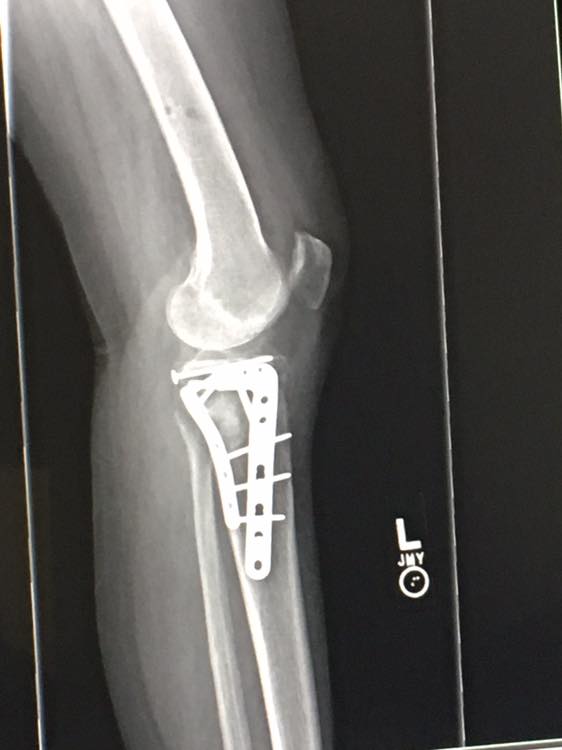

In cases of severe displacement, open fractures, or when conservative methods fail, surgery may be required. Surgical options include:

- Open reduction and internal fixation (ORIF) with pins, plates, or screws

- External fixation devices for complex fractures

Impacted Boxer’s Fracture Requiring Fixation

Surgical treatment is indicated for those fractures with unacceptable angulation or rotation, or a reduction that is not stable in a splint or cast. Surgical fixation methods range from transmetacarpal or interosseous pinning to plate and screw fixation. High level athletes may opt for internal fixation to allow for the potential of earlier return to play. K-wire fixation is often used for better cosmetic results. Surgical fixation adds the usual surgical risks of infection, neurologic injury, and bleeding, as well as the risks of hardware failure and extensor mechanism injury.